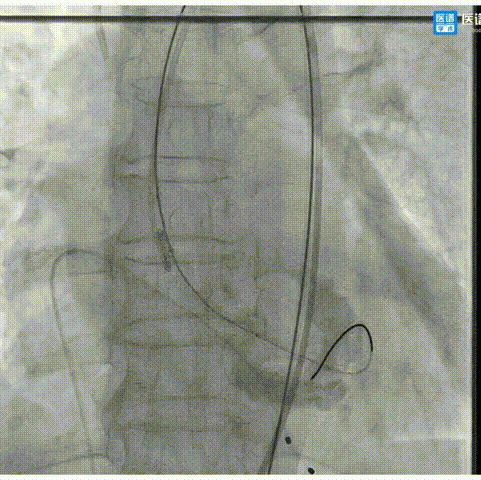

1.以左侧股动脉为辅入路,并在造影指导下穿刺右侧股动脉为主入路;

2.主动脉根部造影,可见瓣口开闭尚可,心室内轻微反流,主动脉及心脏情况整体较为稳定;

3.直头导丝跨瓣,通过交换导丝将猪尾导管引入左室。超声评估示最大流速4.5m/s,最大跨瓣压差约79mmHg;

4.180次/分快速起搏下以18mm TaurusAtlas球囊进行预扩张,扩张时无明显腰征;

6.造影评估示瓣膜植入深度、工作形态良好、微量瓣周漏,遂予以全部释放;